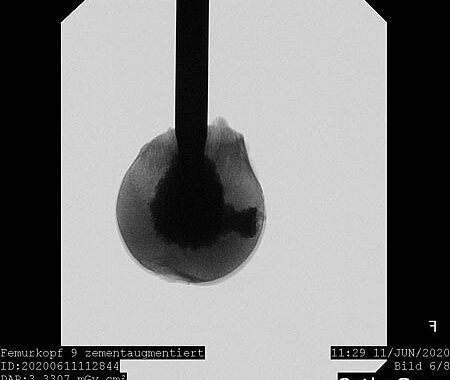

Our research currently focuses on optimizing mineral bone cements for clinical use. The necessary basic components for calcium phosphate and magnesium phosphate cements are combined in such a way that the desired properties – such as sufficient viscosity for injection and subsequent hardening with high load-bearing capacity – are optimized.